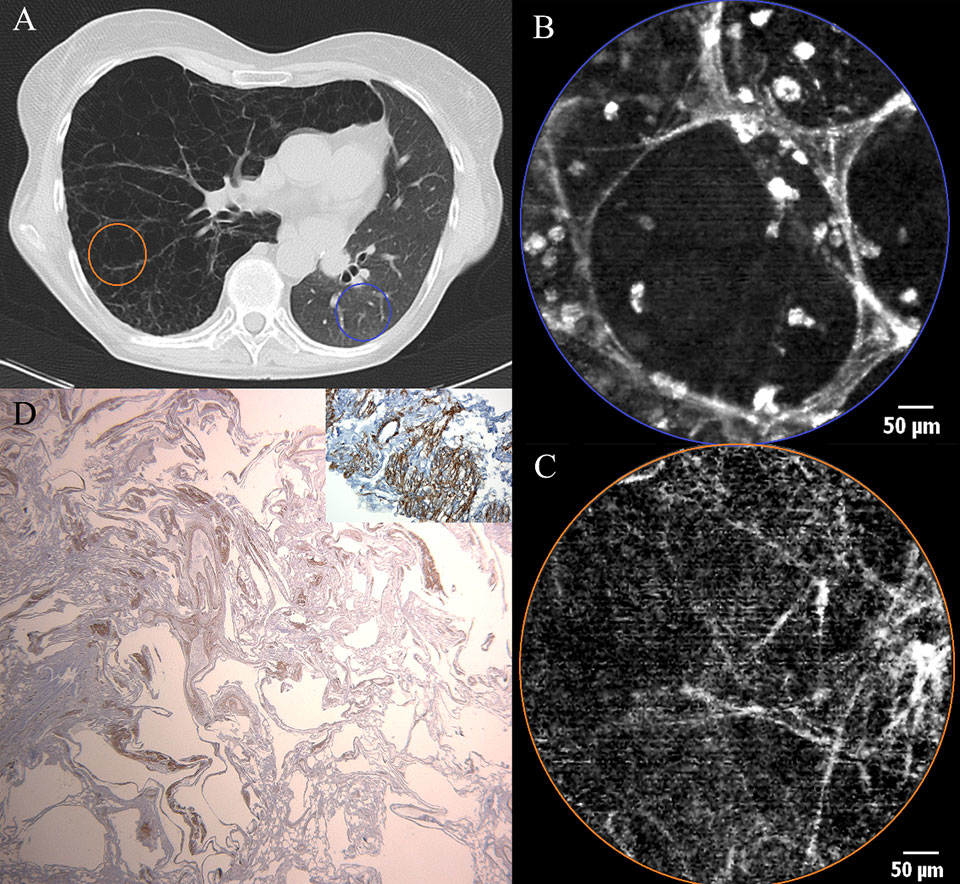

Figure 4

a) Chest CT scan of a patient with exacerbating dyspnoea, showing bilateral honeycombing with right sided predominance (filled arrow), patchy areas of ground glass opacity (open arrow) superimposed by thickened inter- and intra-lobular septal fibres. b) pCLE imaging performed ex vivo after introduction of the probe in the BAL sample. A large (200 µm) clump of fluorescent material (glycoprotein) (asterisk) is surrounded by smaller (20-30 µm) round opacities (arrow) with increased autofluorescence (macrophages). c) Histopathology on a thoracoscopic lung biopsy sample. The basic alveolar structures have been preserved (arrow). Presence of eosinophilic, PAS stain positive material containing crystalised cholesterol (asterisk).

The case of a 63-year-old non-smoking female patient with diffuse interstitial lung disease of unknown aetiology added more to this concept. Chest CT scan showed bilateral honeycombing with right sided predominance, patchy areas of ground glass opacity superimposed by thickened inter- and intra-lobular septal fibres (fig. 4a). During the flexible bronchoscopy, bronchoalveolar lavage (BAL) was performed for immunological research. When the confocal probe was inserted into the lavage fluid after bronchoscopy, the formerly described pattern was recognised, suggesting, indeed, an alveolar proteinosis (fig. 4b). Thoracoscopic lung biopsy confirmed the diagnosis of an alveolar proteinosis afterwards (fig. 4c).